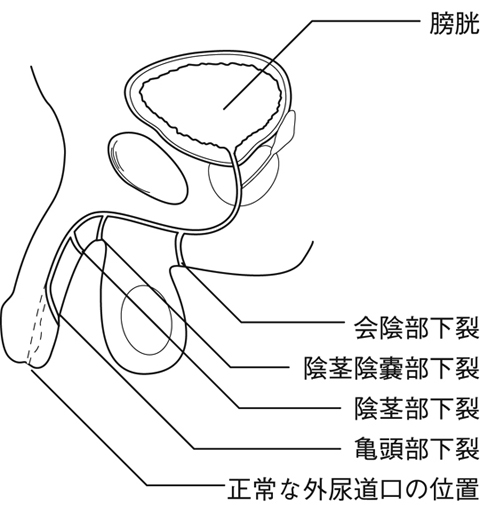

尿道下裂とは コトバンク